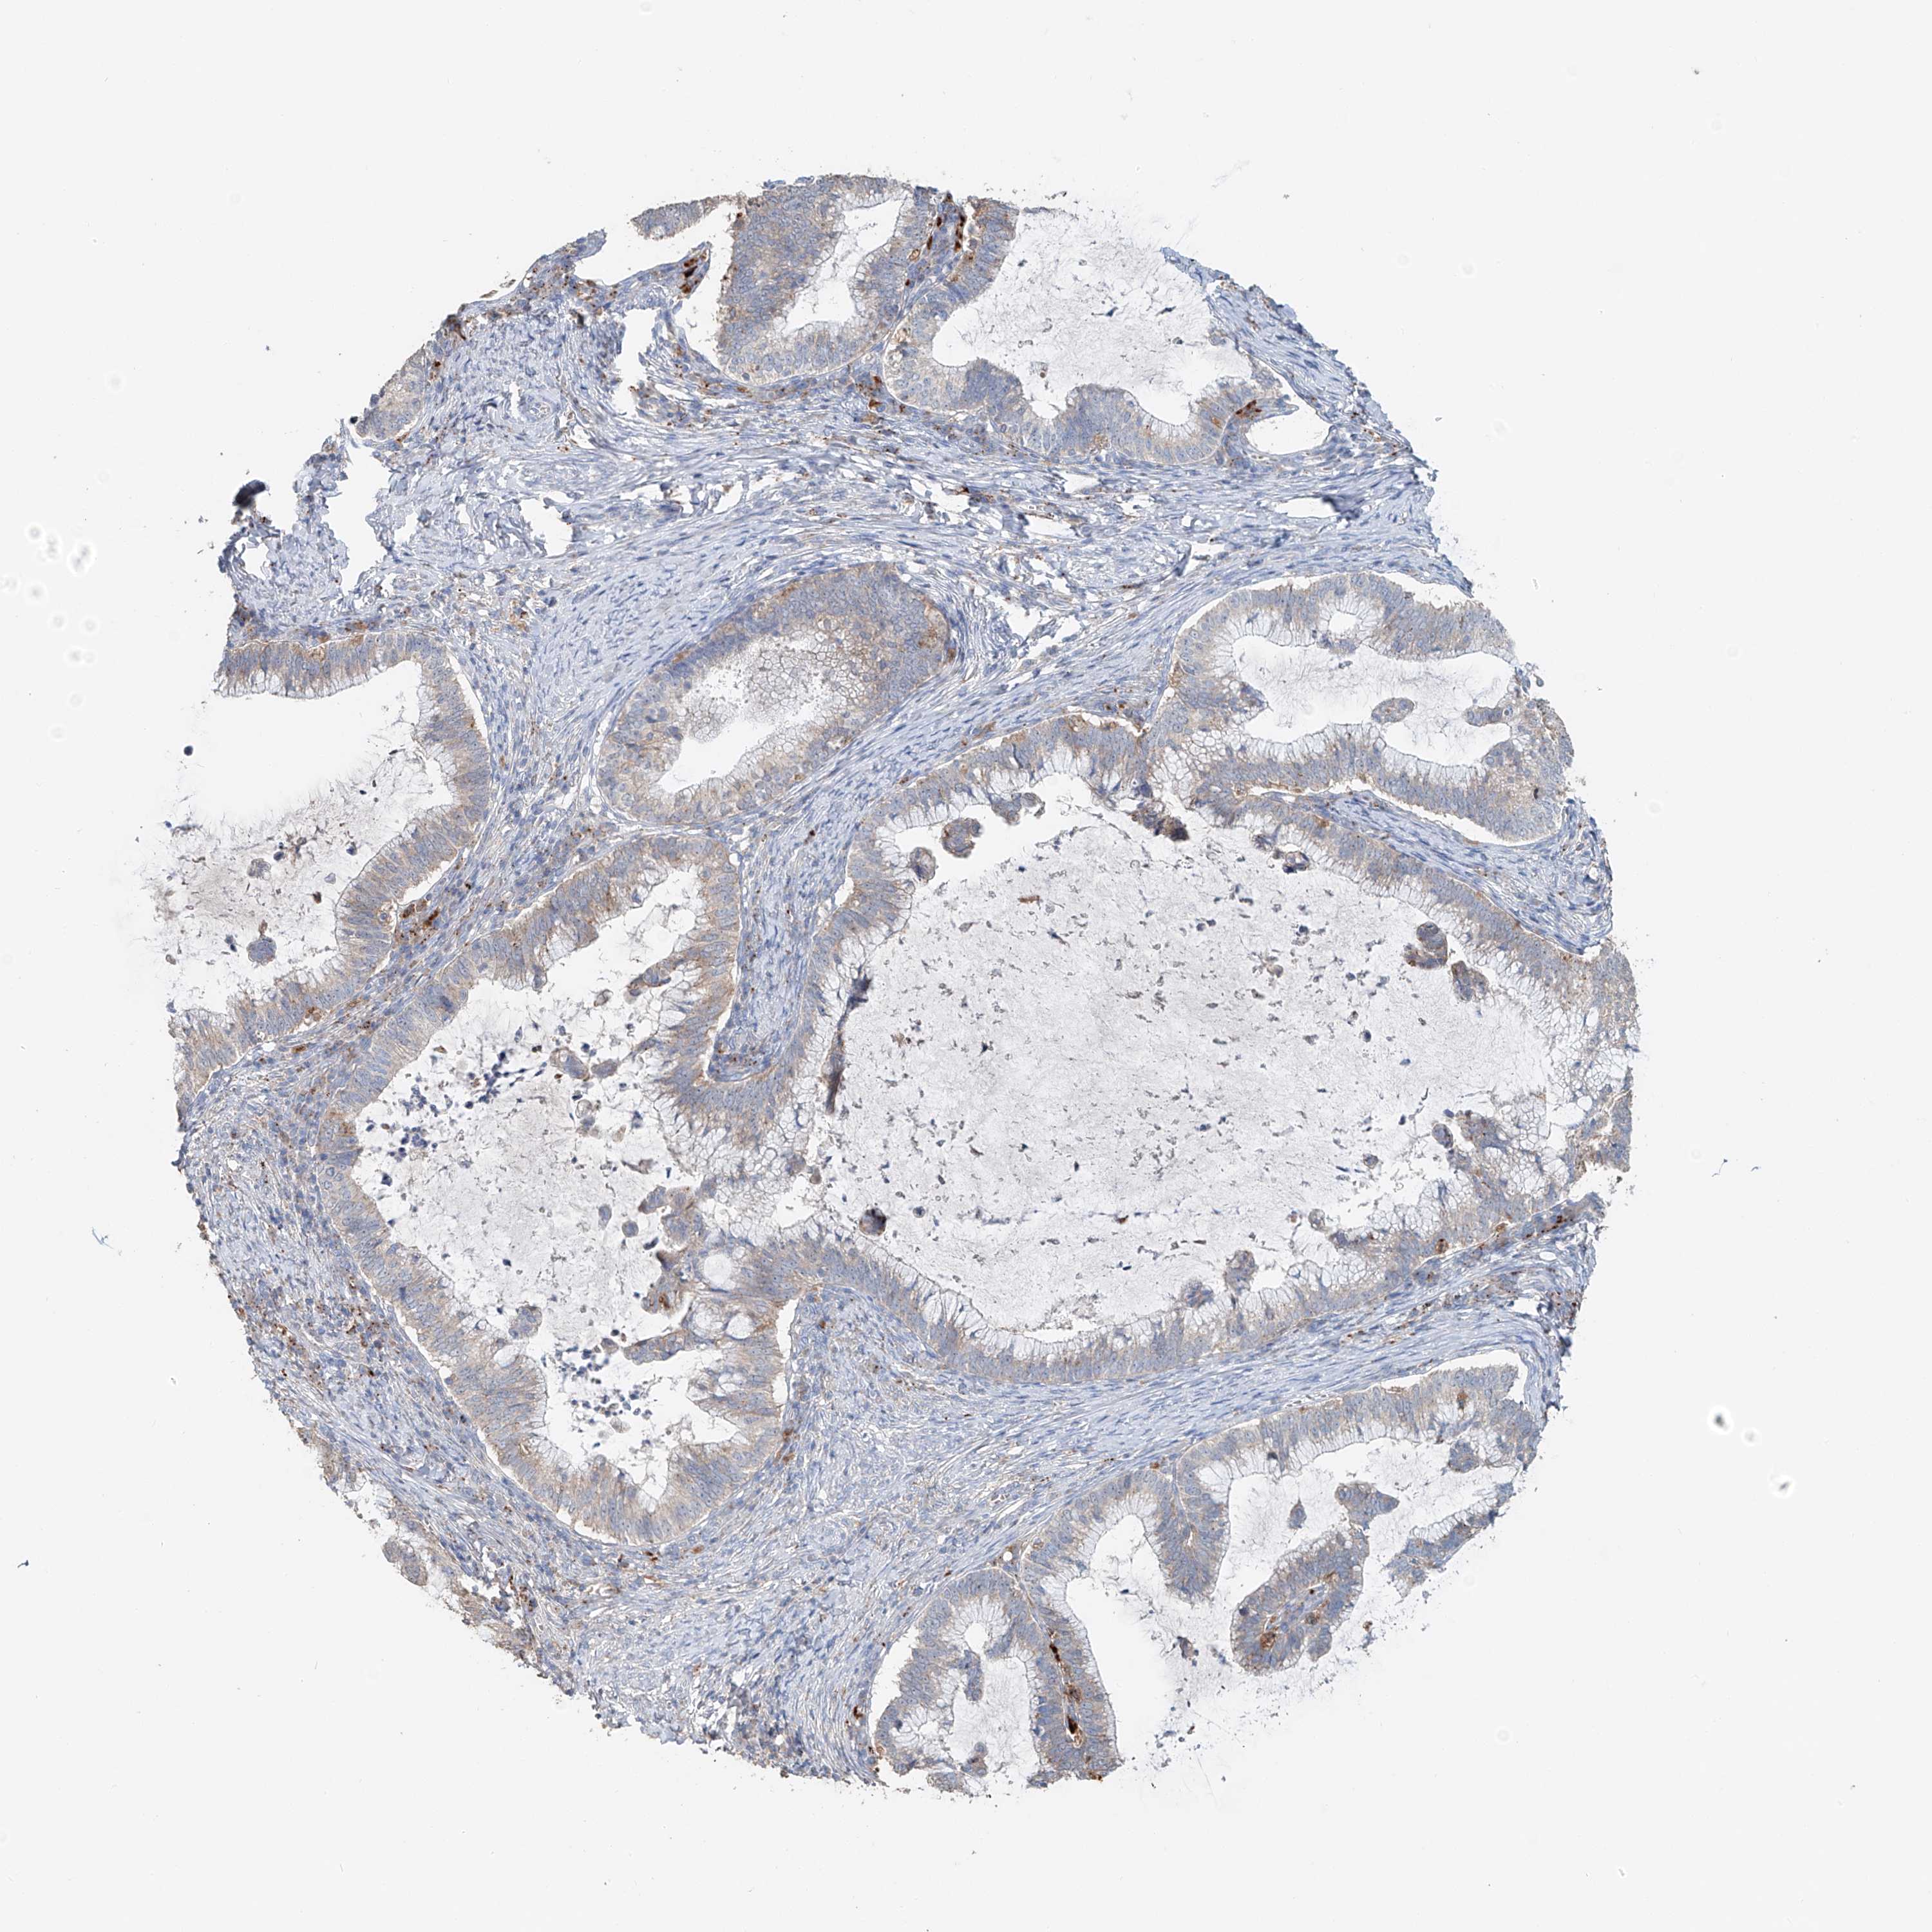

CERVICAL CANCER - Protein expressioni

A mouse-over function shows sample information and annotation data. Click on an image to view it in a full screen mode. Samples can be filtered based on level of antibody staining by selecting one or several of the following categories: high, medium, low and not detected. The assay and annotation is described here.

Note that samples used for immunohistochemistry by the Human Protein Atlas do not correspond to samples in the TCGA dataset.

Antibody stainingi

Antibody staining in the annotated cell types in the current human tissue is reported as not detected, low, medium, or high, based on conventional immunohistochemistry profiling in selected tissues. This score is based on the combination of the staining intensity and fraction of stained cells.

Each image is clickable and will lead to virtual microscopy that enables deeper exploration of all samples and also displays staining intensity scores, fraction scores and subcellular localization as well as patient and tissue information for each sample.

Antibody HPA014933

Staining

High

Medium

Low

Not detected

Intensity

Strong

Moderate

Weak

Negative

Quantity

>75%

75%-25%

<25%

None

Location

Nuclear

Cytoplasmic/membranous

Cytoplasmic/membranous,nuclear

Squamous cell carcinoma, NOS

Adenocarcinoma, NOS